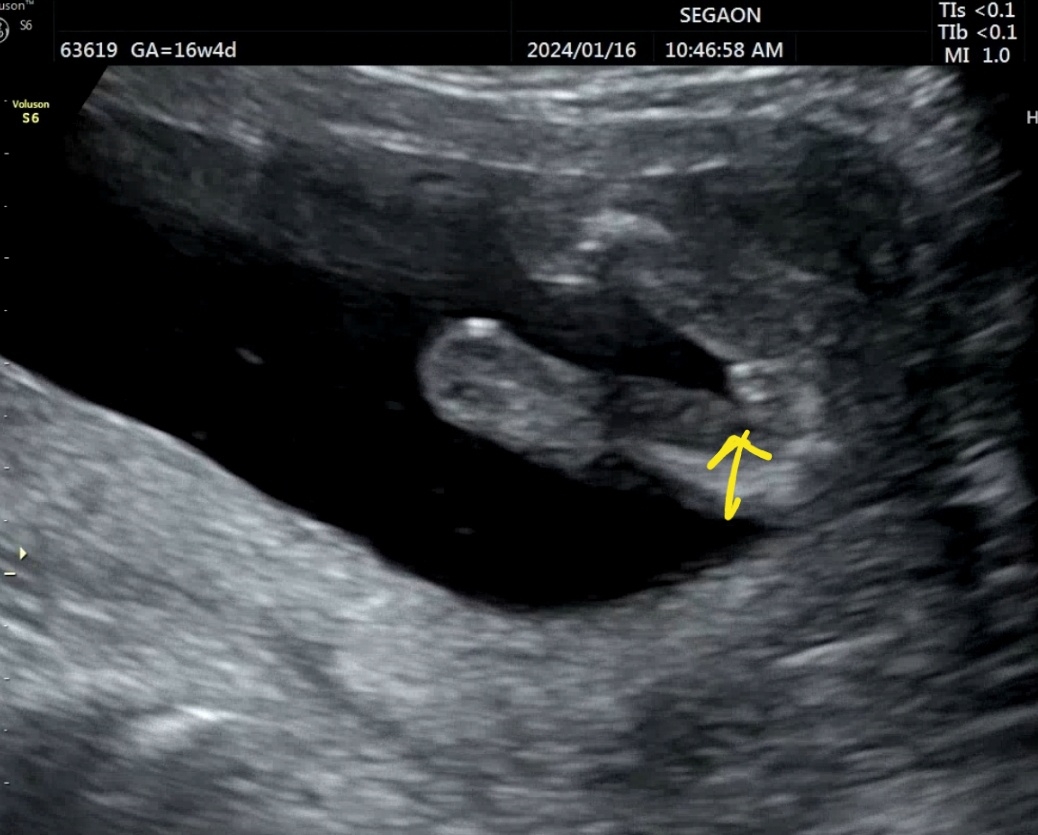

뭘까요??ㅠㅠ

고츄일까요 탯줄일까요? 🤣

고츄같아요!!!!!!! 저희 아가도 저렇게 뿅 있었답니다😊😊

오 정말요~? 넘커서 고추맞나 싶었네용ㅎㅎ